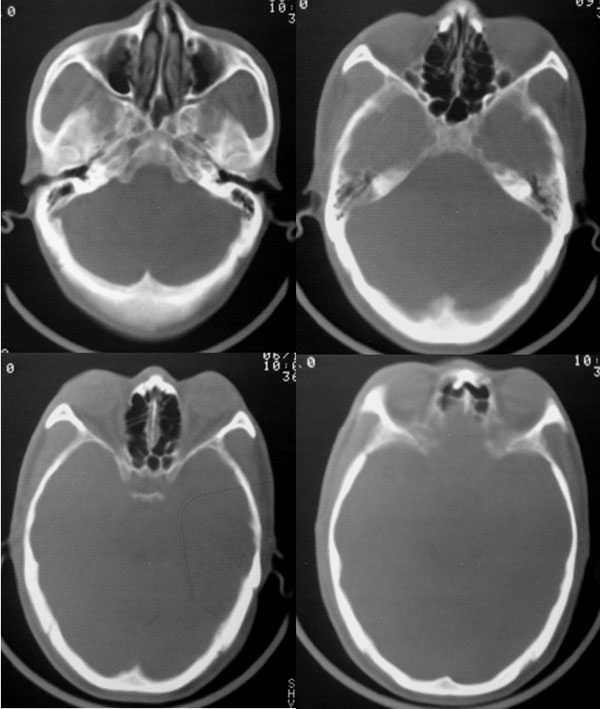

以下是引用dyqct在2006-11-9 15:04:00的发言:[br]左枕叶、双顶叶各见一处似三角形低密度区,边界尚清楚,无占位效应,累及皮质,白质侧未见灰质影。余所见未见异常。[br]考虑:1、脑软化灶;[br] 2、不支持脑裂畸形,该病病变区两侧应有灰质带——即灰质异位,临床上常有顽固性颠痫。当然了脑软化灶也偶会出现颠痫。

以下是引用守望可可西里在2006-11-9 15:06:00的发言:[br][br] 1.左侧枕叶低密度与侧脑室相通,考虑开唇型脑裂畸形。[br] 2.双侧顶叶低密度考虑局部脑沟异常扩大,发育问题。